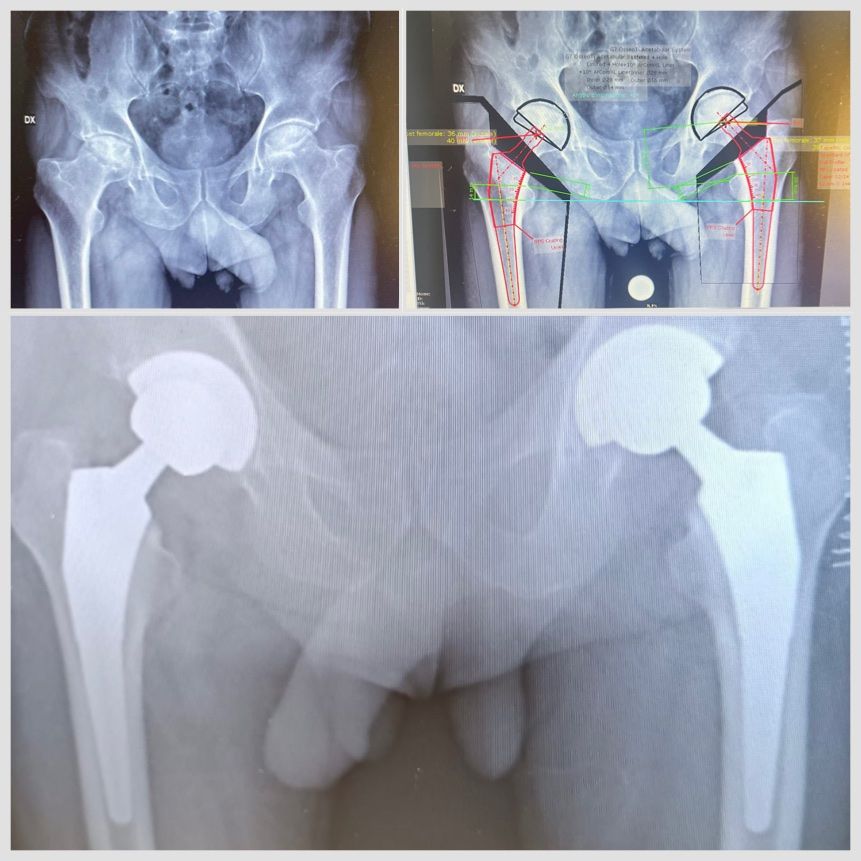

• Chirurgia protesica mini-invasiva di anca e ginocchio a Firenze – interventi eseguiti con approcci che riducono il trauma chirurgico, rispettano i tessuti e favoriscono un recupero più rapido.

• Planning pre-operatorio 2D e 3D – pianificazione computerizzata che assicura la massima precisione nella ricostruzione della biomeccanica articolare.